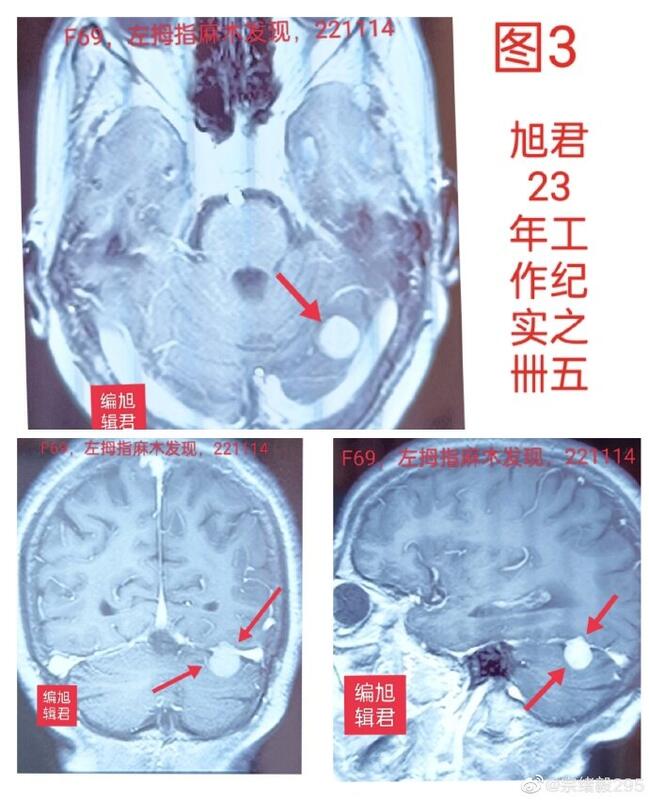

图3:某患者69岁,左手麻木发现小脑膜瘤,麻木与肿瘤无相关性。

图-3